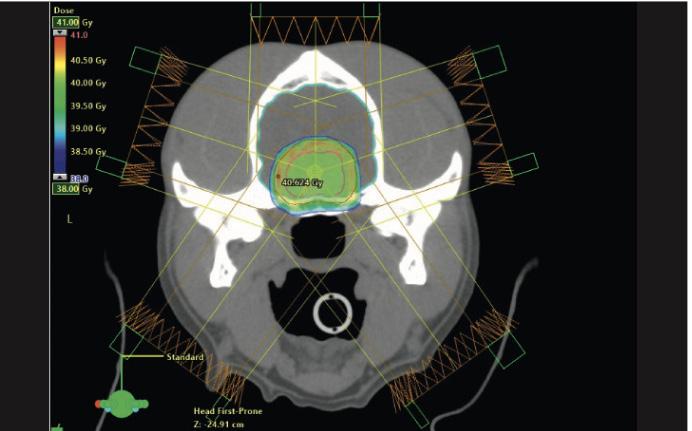

View of a radiation plan of two patients with pituitary tumors. The image at the top shows a regular irradiation protocol with a mean dose of 10x4 Gy; the image at the bottom shows the “boost” dose in the tumor center mentioned in the text with 15 percent more dose.